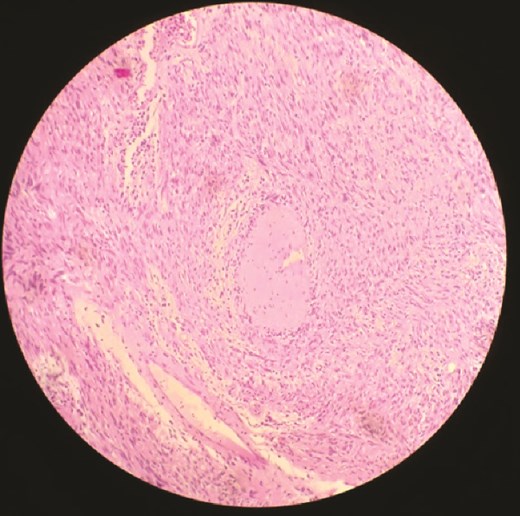

Histopathology demonstrated proliferation of spindle-shaped cells arranged in palisading patterns characteristic of Antoni A regions, intermixed with looser Antoni B areas. The tumor was vascularized by thick-walled, hyalinized vessels, and inflammatory infiltrates were present. These features were highly suggestive of schwannoma. Immunohistochemical analysis revealed strong positivity for S100 protein and smooth muscle actin, while staining negative for desmin and CD34, confirming the diagnosis. The postoperative course was uneventful, and the patient was discharged in stable condition.

Microscopically, the tumor is made out of elongated cells arranged in alignments known as palisades that take one of two patterns: Cells in Antoni type A are displayed in an arranged and firm pattern, while cells in Antoni type B are dispersed loosely within an edematous matrix (Figs 3 and 4). Both of these patterns can coexist and malignant changes are rare [6]. Definite diagnosis is made through histopathological examination and immunohistochemistry [1]. S100 protein positivity and vimentin present hallmark of schwannoma [2].

In our case, histopathological findings showed spindle cell proliferation with Antoni A and Antoni B regions, with the presence of S100 protein and vimentin in the immunohistochemical study.